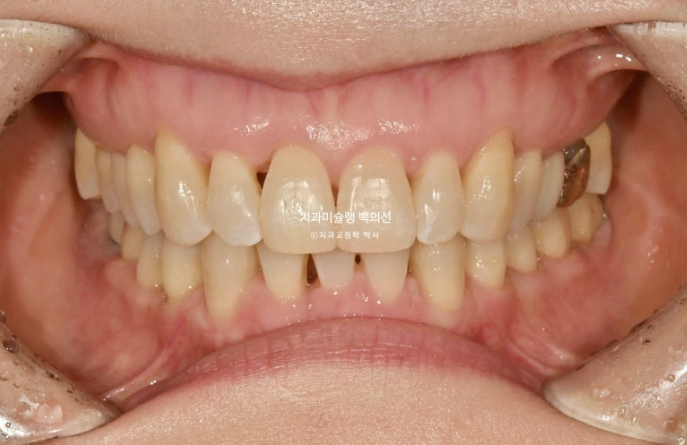

이제 전 후 비교 보겠습니다.

24.09~25.09

앞니가 깊게 물리는 과개교합이 개선되었습니다.

특히 뿌리가 보일 정도로 솟아내려와있던 파란 화살표 앞니가 건강하게 제 위치로 함입이 되고 노출된 뿌리 부분이 다시 잇몸속으로 안정적으로 들어갔습니다.